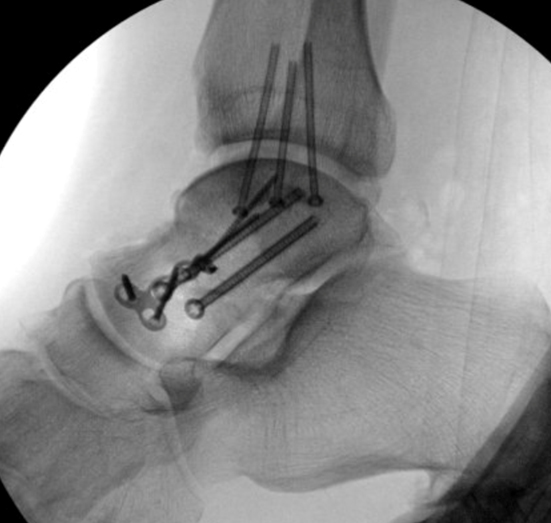

TOTAL ANKLE REPLACEMENT :: ORIF CALCANEUS :: ORIF ANKLE FRACTURE DISLOCATION :: COMPLEX BUNION AND LESSER TOE CORRECTION :: TALUS FRACTURE -1 :: TALUS FRACTURE -2 :: LISFRANC REPAIR :: COMPLEX TRIPLE ARTHRODESIS 1 :: COMPLEX TRIPLE ARTHRODESIS 2 :: MINIMALLY INVASIVE BUNION REPAIR 1 :: MINIMALLY INVASIVE BUNION REPAIR 2 :: ARTHROSCOPIC CARTILAGE REPAIR :: TENEX SPUR DEBRIDEMENT :: Haglunds Debridement and Achilles Repair